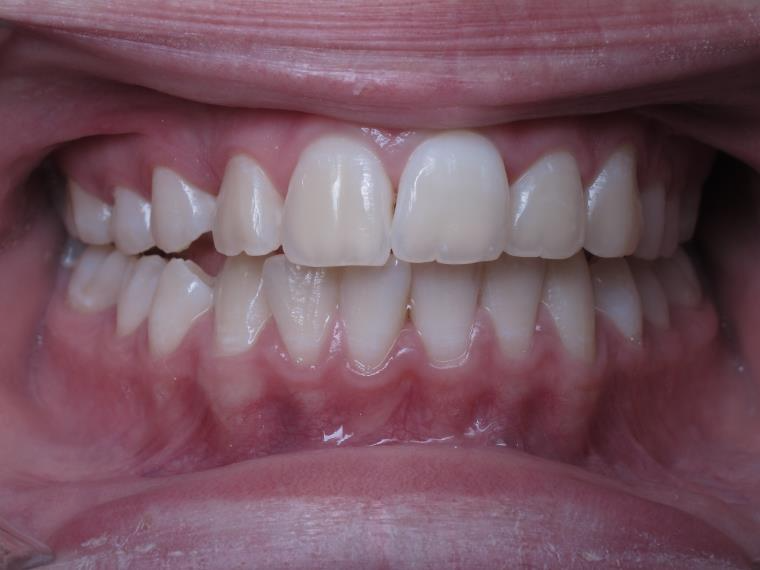

inversion des dents posterieur cote gauche

bilan début et fin de traitement